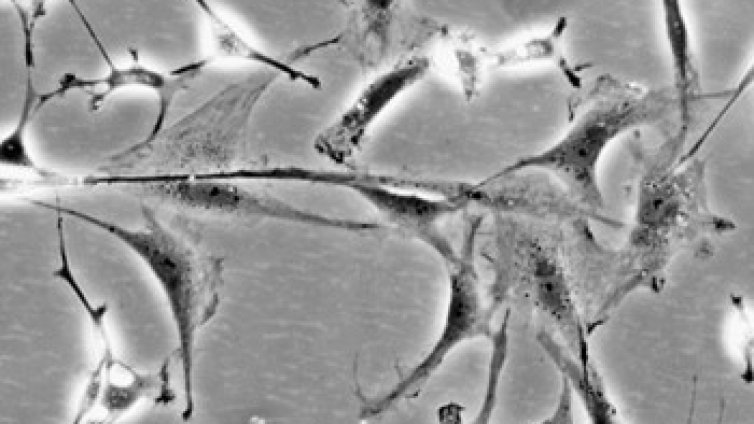

Литий е изпробван срещу болестта на Паркинсон